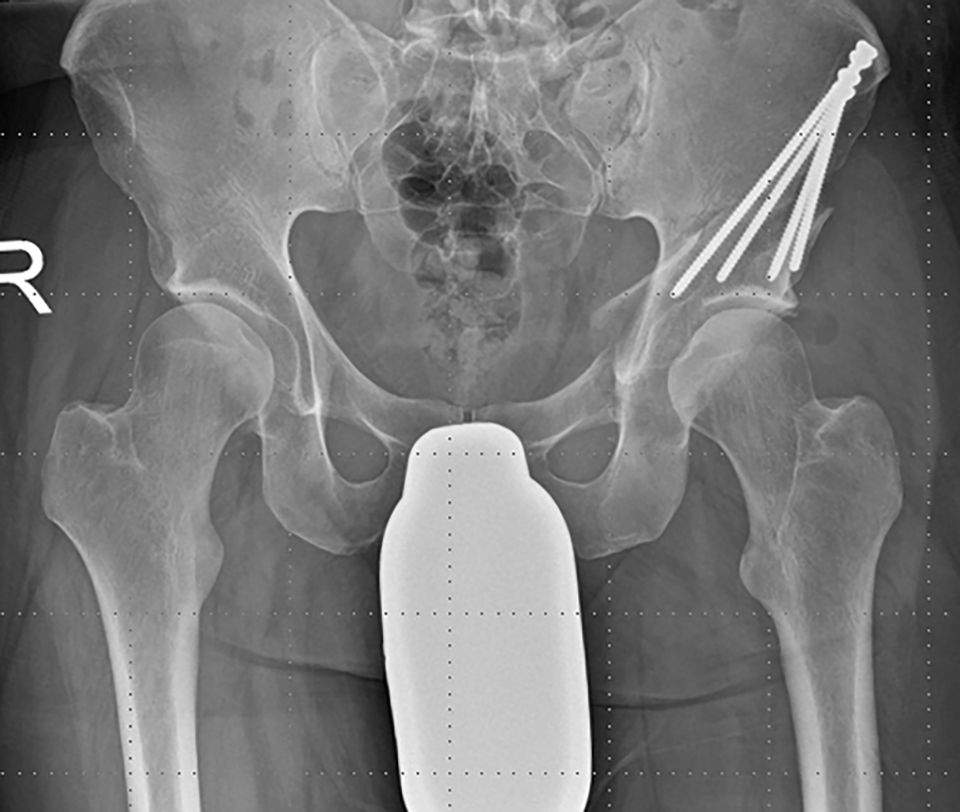

To avoid postoperative limitation in ROM or femoroacetabular impingement the freedom of motion after reorientation and before definite fixation of the acetabular fragment should be checked with minimum of 120° flexion and 30° internal rotation in 90° hip flexion. If an optimal acetabular reorientation and adequate ROM has been achieved the acetabular fragment is definitely fixed with four 4,5mm screws. The screw placement is verified with fluoroscopy to verify their extraarticular position (Fig. 16).

Arcoxia 90 mg is provided for 21 days postoperatively as a prophylaxis against heterotopic ossification. Antithrombotic medication Fragmin P forte 1x1 sc. is given until normal mobilization is achieved. Postoperative mobilization is performed under 50% weight-bearing with crutches for 4 weeks and progressed to full weight bearing until the 6th post-operative week. To check the stability of postoperative fixation and bone healing, an ap pelvic x ray should be obtained before full weight bearing (Fig. 19, 20). Low-impact sports can be initiated after the 6th postoperative week. No limitations regarding the ROM are given, but physical therapy is gently started after 2-4 weeks.